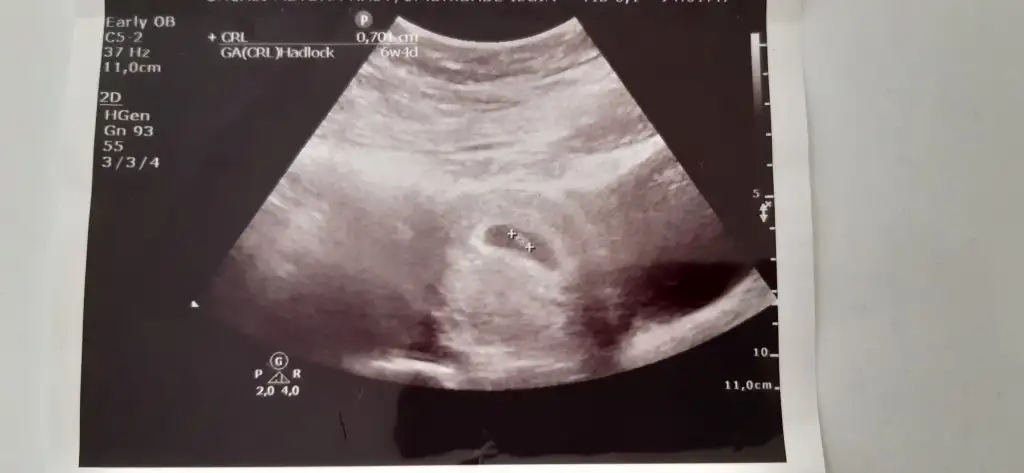

Mrb 13 haftalık cinsiyetine bakarmısınız